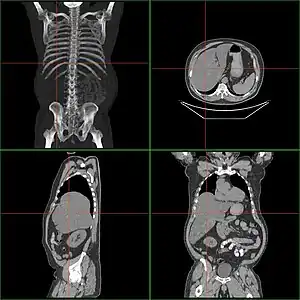

Computed tomography finding of hepatomegaly. -

Computerized tomography (CT) can help to obtain accurate anatomical information, in individuals with hepatomegaly for the purpose of a complete diagnosis.[21]